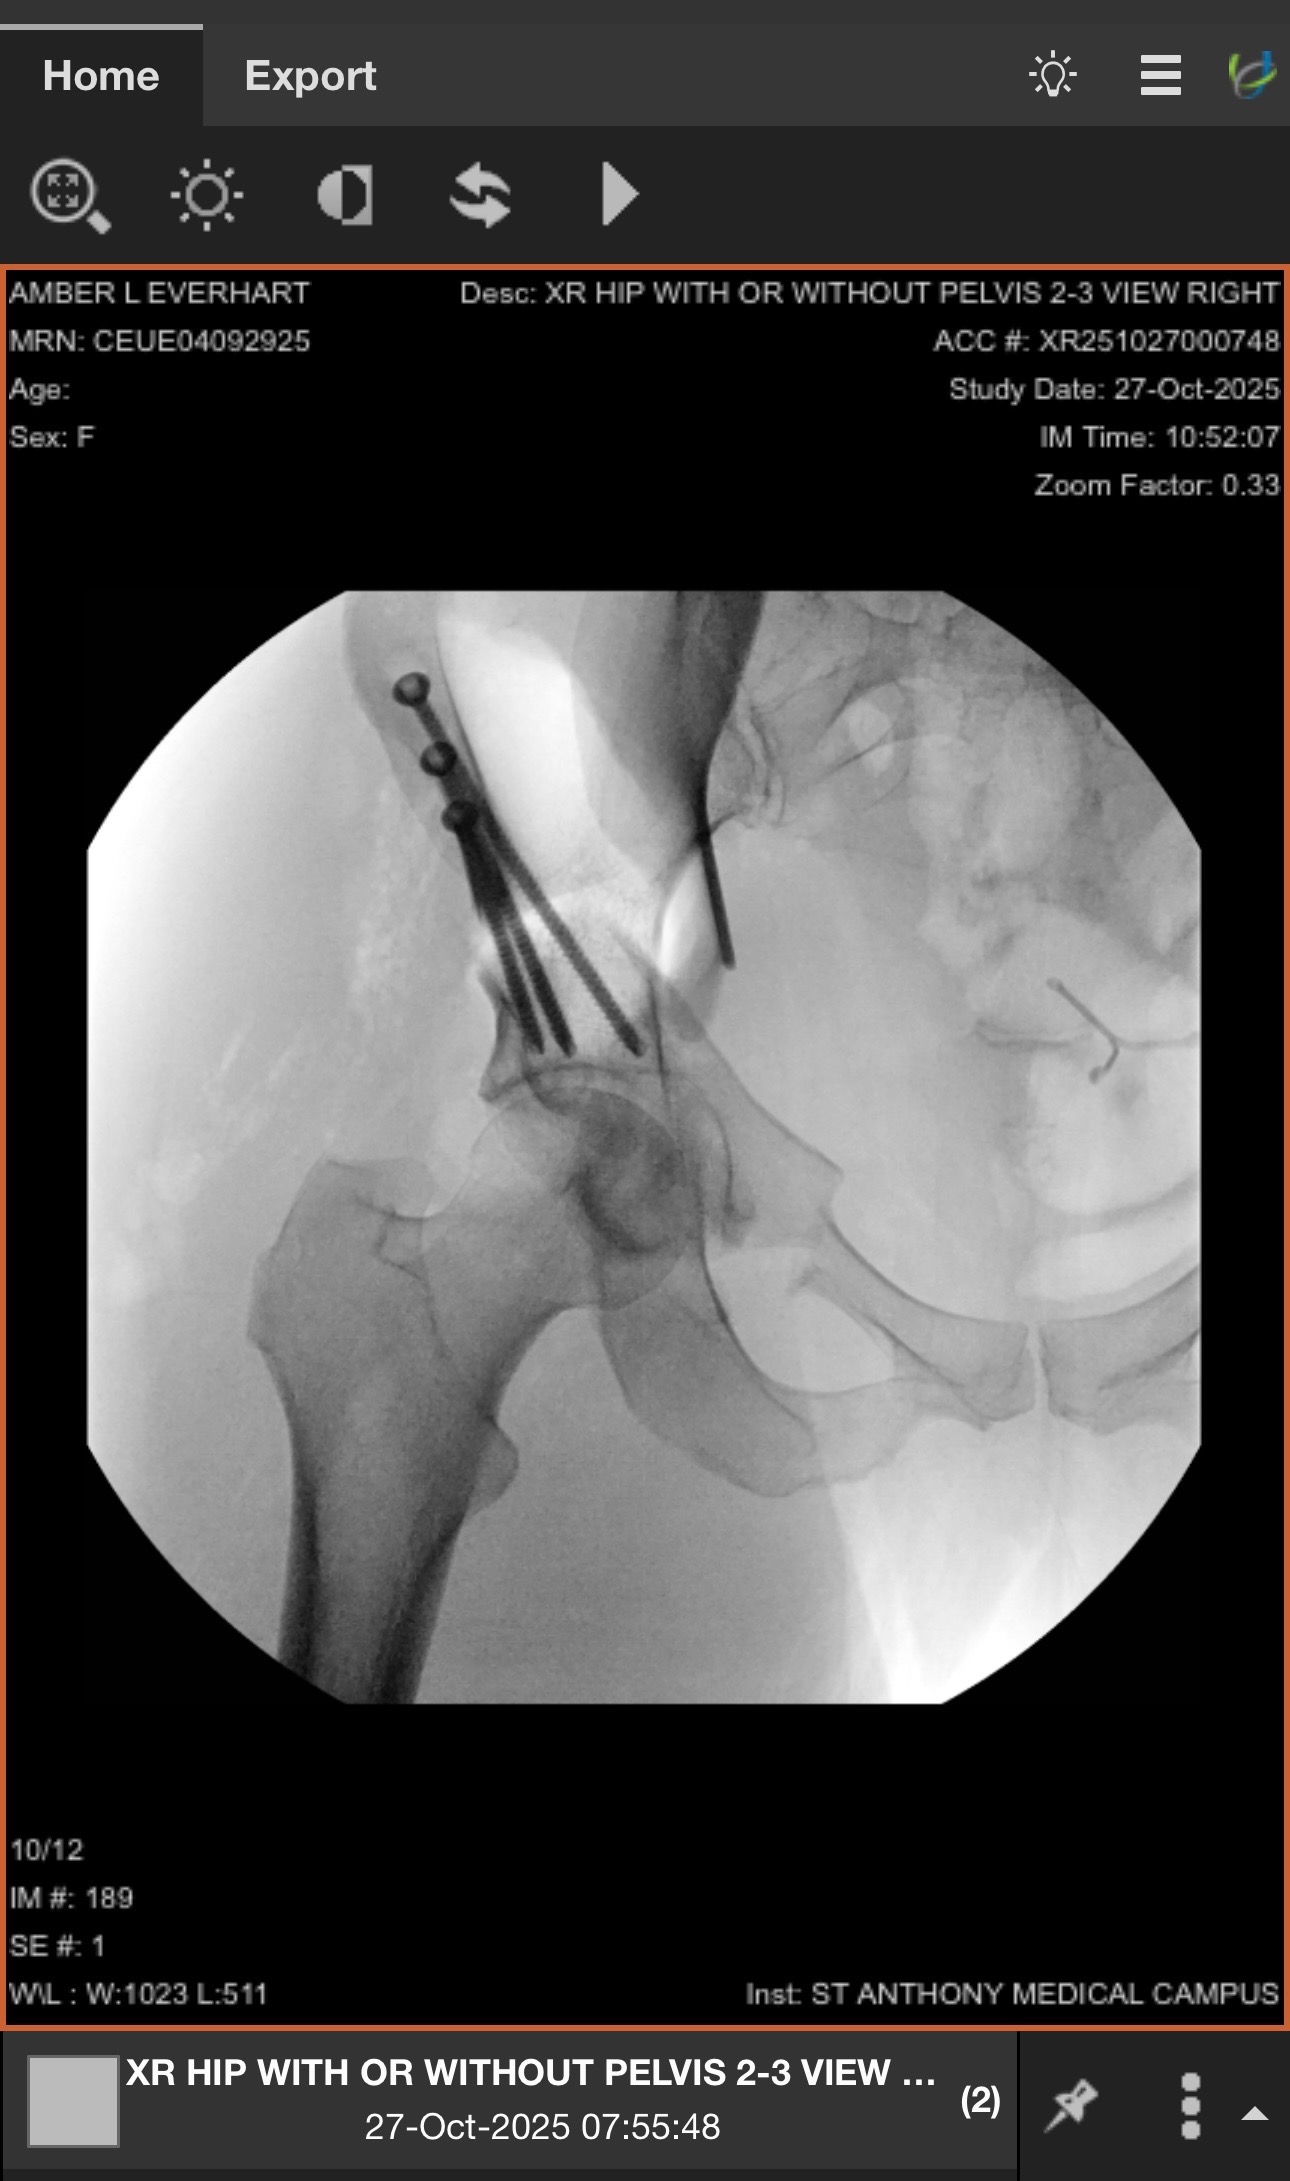

For years, Amber has been managing a complex and often invisible battle with a chronic illness: Ehlers-Danlos Syndrome which has caused a complex amount of other health issues: Ovary Syndrome (PCOS), orthodontic hypotension, and hip dysplasia (with a torn labrum). These conditions, which have deeply impacted her life, have now led to the need for a major, life-changing surgery- a periacetabular osteotomy and hip arthroscopy. Amber has been on crutches all summer, and eventually led to being in a wheelchair, unable to walk.

Due to the faulty connective tissue associated with her EDS, her joints are hypermobile and unstable. This has caused significant wear and tear on her hips, leading to a condition called hip dysplasia. In her case, the hip socket is too shallow and doesn't properly cover the ball of the femur, causing daily pain, instability, and an increased risk of long-term arthritis.

The solution is a major surgery called a periacetabular osteotomy (PAO). This procedure involves cutting the pelvis around the hip socket and repositioning it to better cover the femoral head. While incredibly complex and difficult, a PAO is a hip-preserving surgery that is her best chance at a pain-free, active life, and will help avoid a full hip replacement in the future.